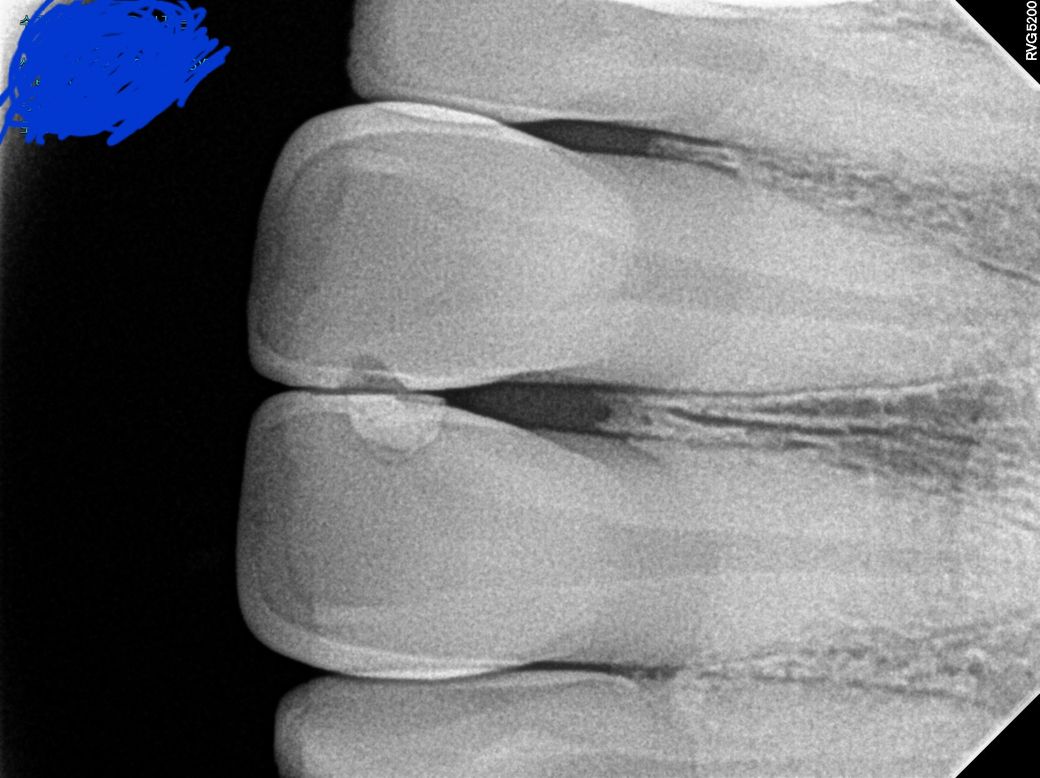

• 3번 째 사진

11,21 번 치아 사이에 파절 및 충치가 생겨있는 것 같습니다. 치료 받으러 가시면 됩니다.

1. 큰 사진이 파노라마 방사선 사진이고, 작은 사진이 치근단 사진이며 치근단 방사선 사진상(노란색으로 표시하신 사진 기준) 왼쪽이 11번 치아, 오른쪽이 21번 치아 입니다. 만약 두 치아를 동일한 재료로 떼우신 거라면 11번은 기존 재료가 떨어져 나간 상태로 보입니다.

2. 특별히 파절은 보이지 않습니다. 11,21번 치아의 뿌리끝 1/3 부위를 가로지르는 검은 선은 코의 연조직상이 겹쳐 보이는 것입니다.